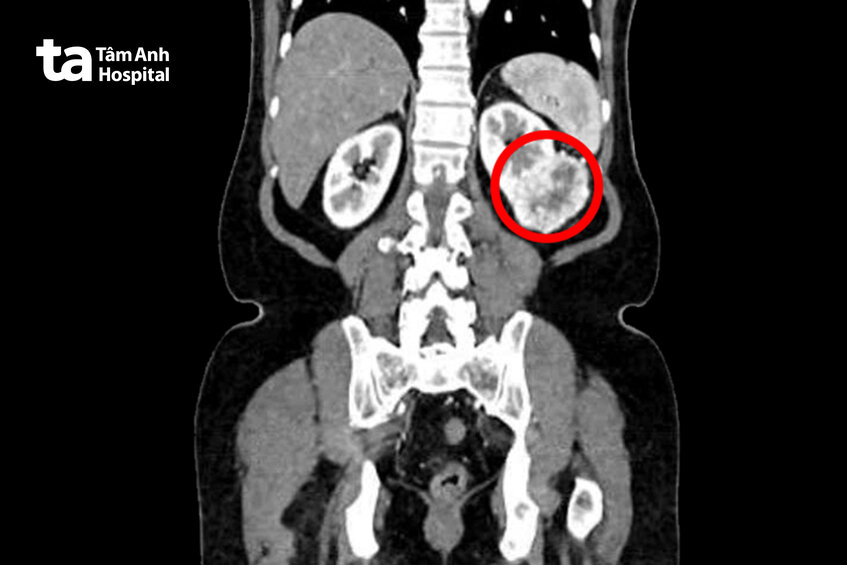

Để chắc chắn hơn, vợ chồng ông đến Bệnh viện Đa khoa Tâm Anh TP HCM kiểm tra một lần nữa. Kết quả chụp cắt lớp vi tính cho thấy, ông Hiền có một khối u ở thận trái kích thước 6 cm, nằm ở 1/3 giữa thận, lấn sâu vào xoang thận, nghi ngờ ung thư tế bào thận, một loại ung thư thường gặp của thận.